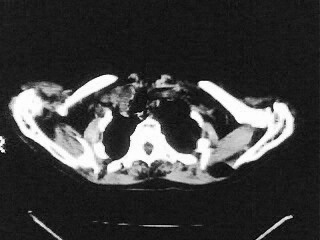

女,79,咳 嗽月余,无其它不适

后纵隔内左心房至肝左叶后方椎体中线偏左巨大软组织包块,其壁均匀比较薄,其内可见宽气液平。

考虑食管裂孔疝。建议钡餐检查